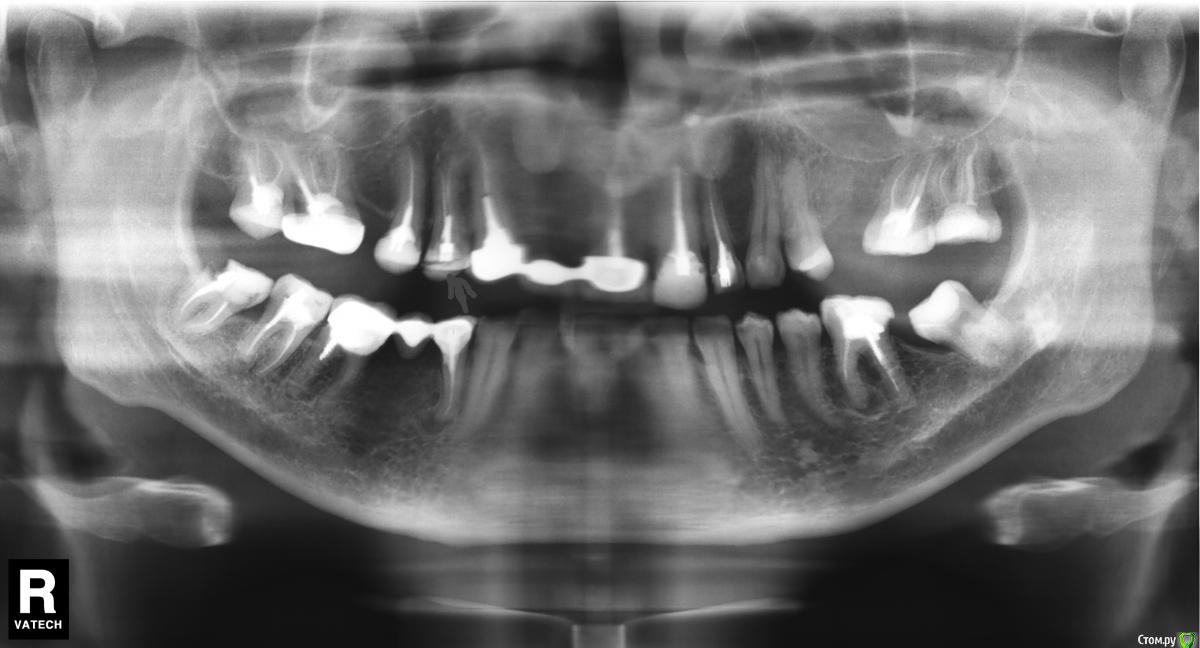

Здравствуйте! На верхней правой  четверке лечили пульпит 2,5 месяца назад . Первые две недели практически не болела. Потом лечили 8-ку на другой стороне челюсти (левая нижняя).

Беспокоит следующее- после лечения этого зуба появились странные ощущения в носу. Как будто постоянное легкое давление, щекотание в правой ноздре.

Гайморитом и ничем подобным не страдал. Насморка нет. Температуры нет. Врач говорит, что на снимках все хорошо.

Снимок прилагаю